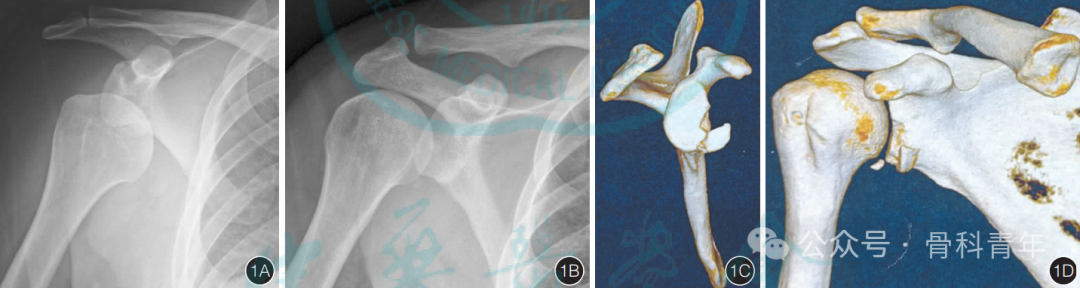

三、临床疗效

研究团队文献发表中已总结了40余例的病例资料,已证实在对肩胛盂前下方骨折的内固定中,腋窝入路可获得良好的治疗效果。

手术切口隐蔽,但由于汗腺发达,存在感染、脂肪液化风险;

无需损伤固有肌腱,创伤小,但解剖复杂,血管存在变异,存在潜在损伤风险;

可显露肩胛盂前下方、肩胛颈及外侧缘;但对肩胛盂后方无法显露。